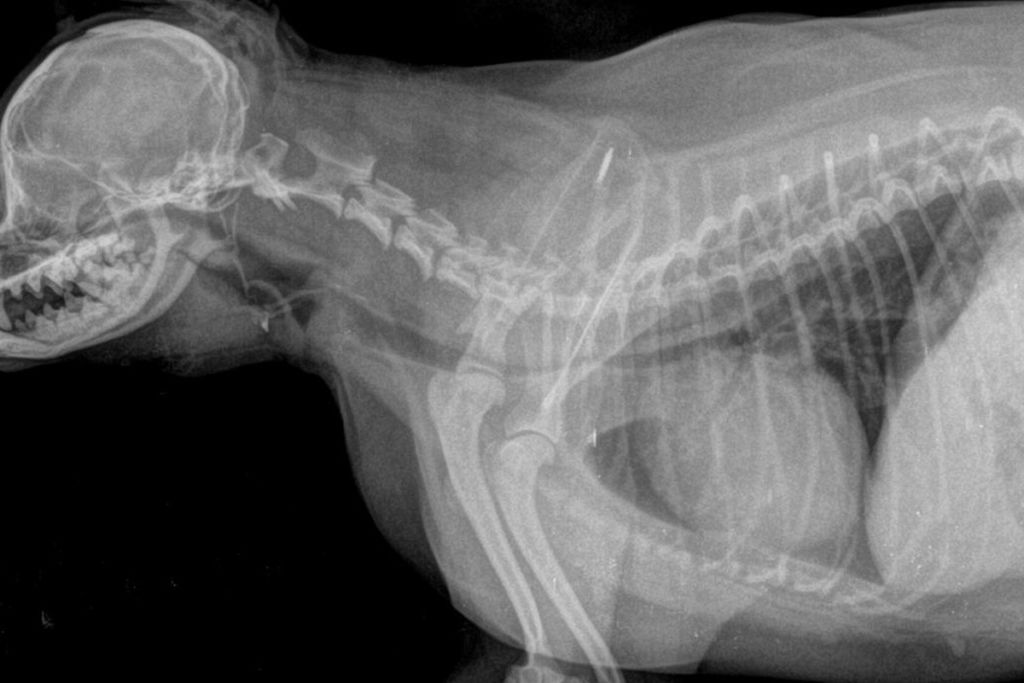

У цій статті я розповім, як зрозуміти, що у собаки розвинувся колапс трахеї, які породи знаходяться в